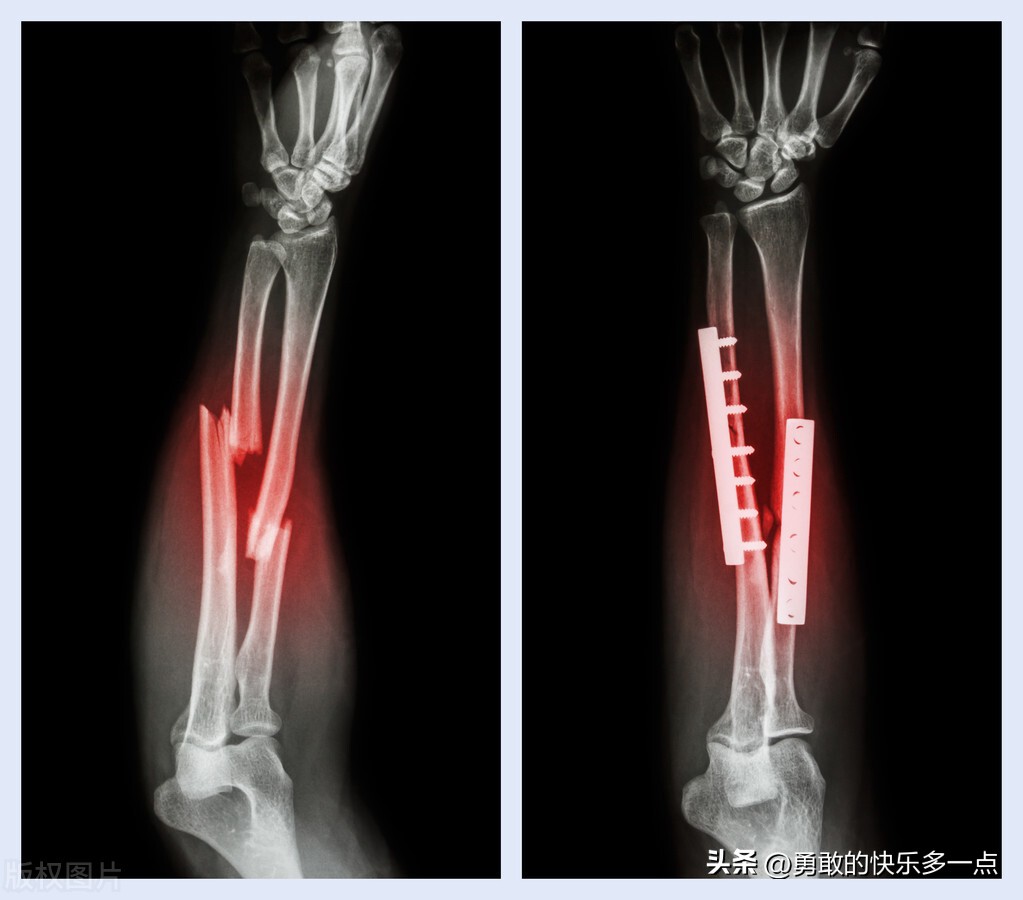

骨折之后,经过一段时间的治疗,超过一般愈合(9个月)所需要的时间,骨折断端仍然没有骨折连接,称为骨折延迟愈合,超过以一般愈合时间而且经过延长治疗时间(3个月)仍没有达到骨性愈合,称为骨折不愈合。

骨折不愈合不能通过延长时间而达到愈合,根据影像学X线表现将骨不愈合分为肥大性和萎缩性,前者骨折断端膨大,硬化,说明曾经有骨再生,由于断端缺乏稳定性造成骨不愈合,后者断端无骨痂,断端分离,萎缩,说明骨折断血运差,无骨再生。

针对骨不愈合,需要切除硬化骨,打通骨髓腔,修复骨缺损,一般需要植骨内固定,必要时还需要加用石膏绷带外固定等给予治疗,部分血供较差的,可能需要考虑进行带血管蒂的骨膜和骨移植以及吻合血管的游离骨膜和骨移植。